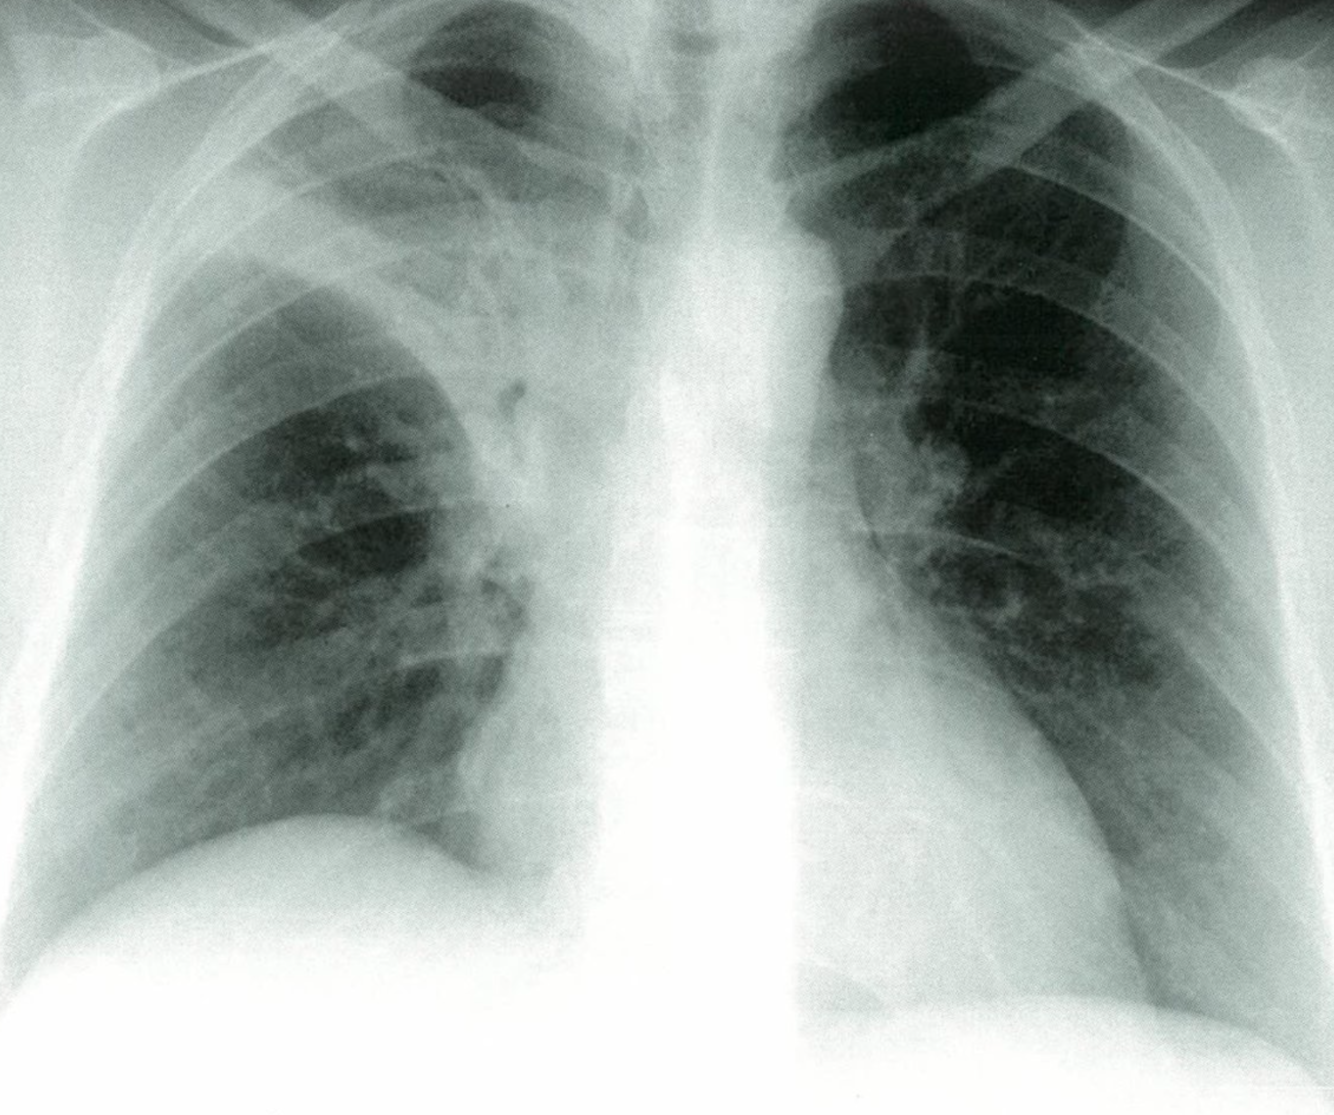

Post-primary tuberculosis

Posteroanterior chest x-ray showing bilateral apical, streaky parenchymal densities (green borders). These are most likely cavernous changes, which may occur during the course of post-primary tuberculosis. The full extent of cavernous formation can not be assessed on an x-ray; a CT scan should be performed.